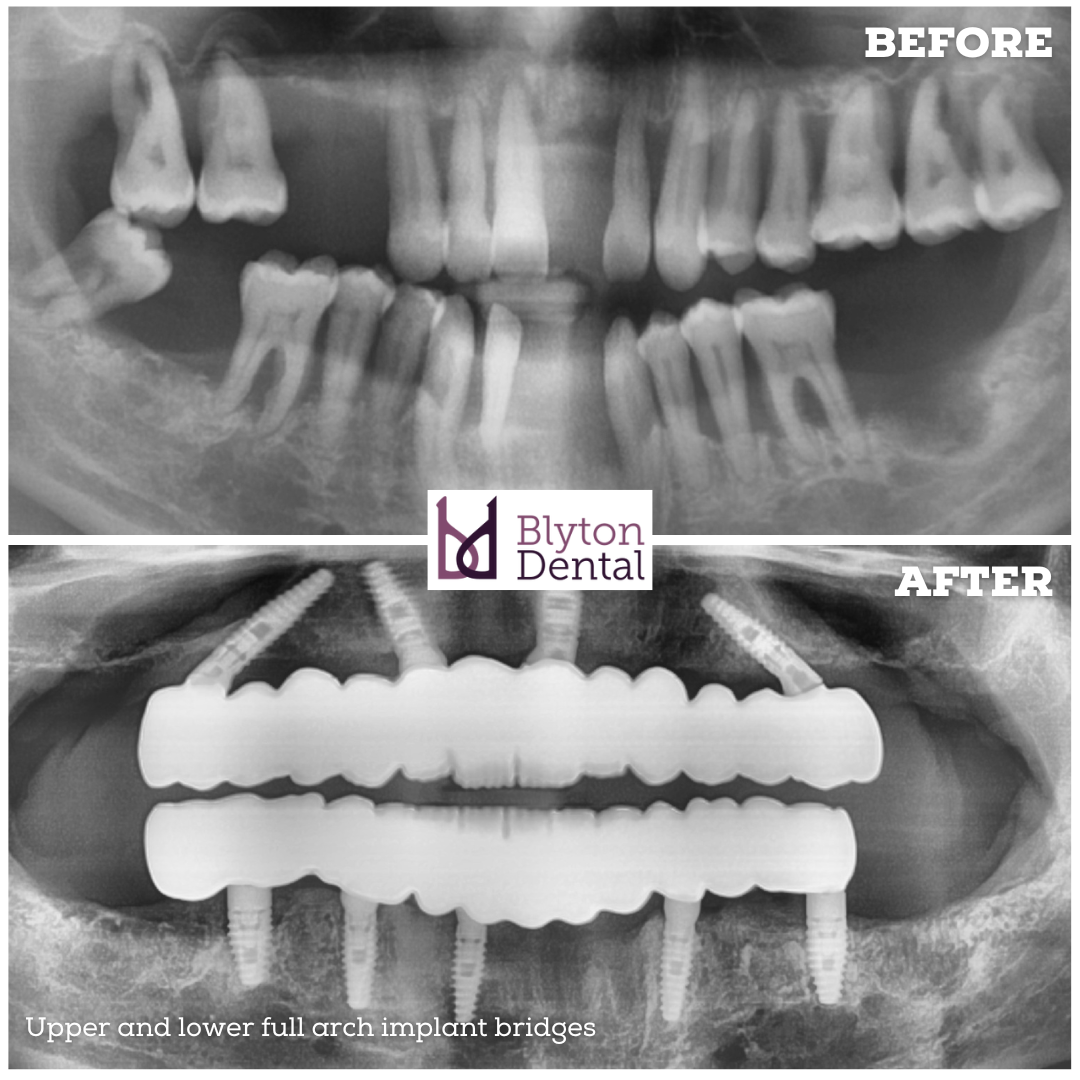

This gentleman came to us with multiple loose teeth which were beyond help.

He wanted to avoid the possibility of wearing dentures.

The remaining teeth were extracted, implants were placed and fixed provisional bridges were delivered.

After six months of healing, we replaced them with long term full arch implant bridges made out of multilayered zirconia for both jaws.

He was very happy with the difference this has made to his smile and chewing efficiency.